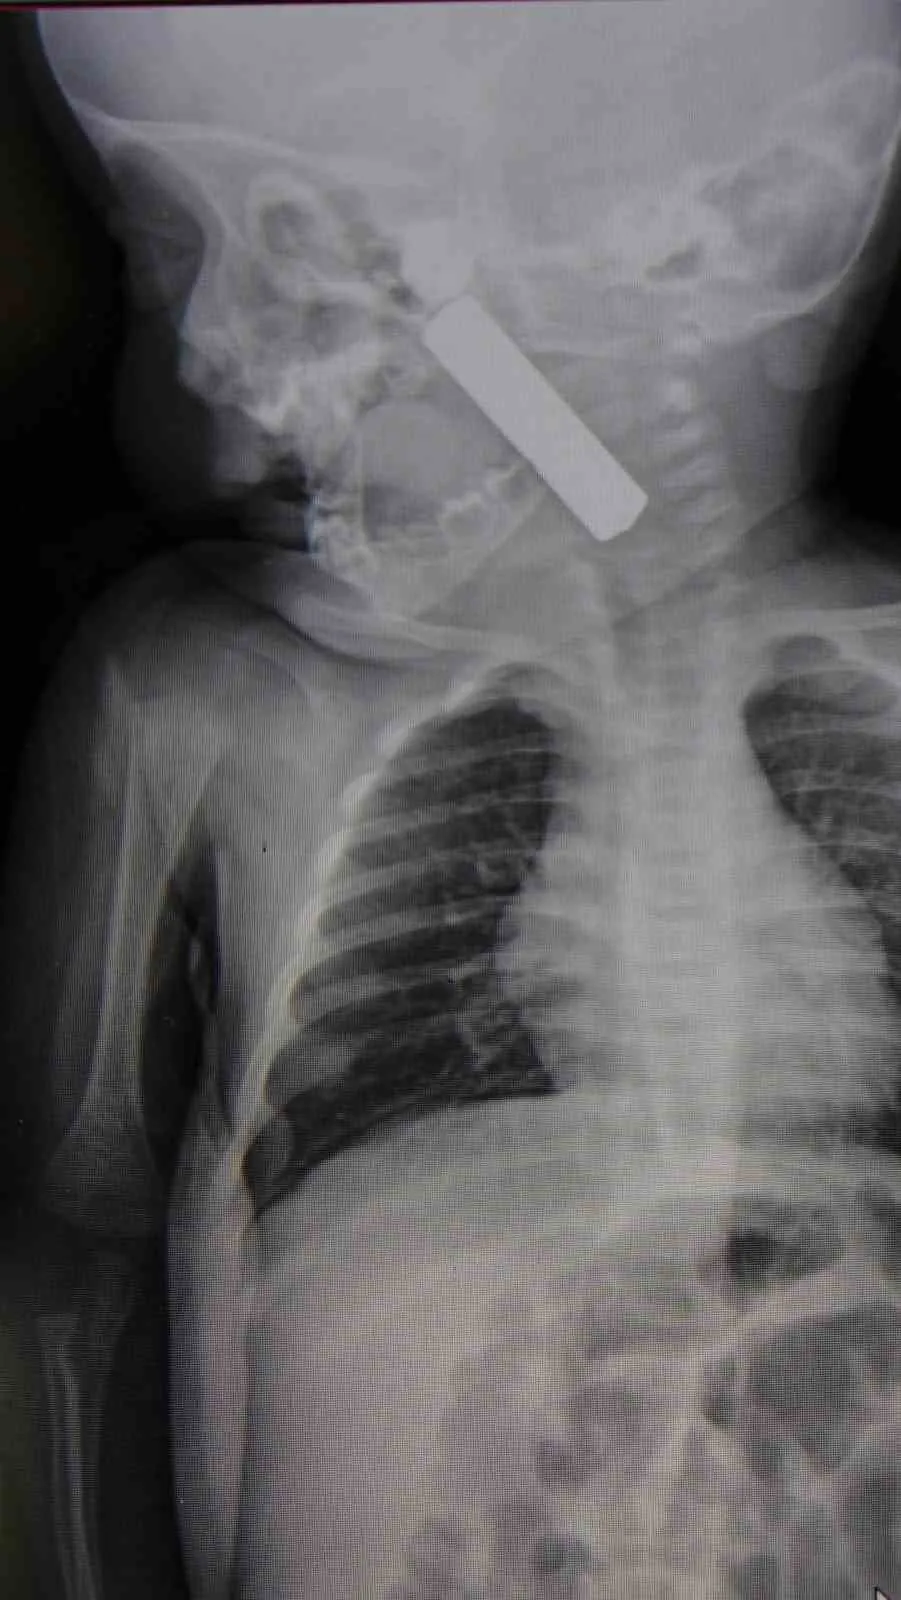

Karaman’da 6 aylık bebeğin boğazına kaçan kumanda pili, ameliyatla çıkarıldı. Edinilen bilgiye göre, kusma şikayeti ile ailesi tarafından Karaman Eğitim ve Araştırma Hastanesi acil servisine getirilen 6 aylık E.A. isimli kız bebeğin, yapılan muayene ve tetkiklerde boğazında kumanda pili kaçtığı tespit edildi. Solunum sıkıntısı da yaşayan bebek hemen ameliyata alındı. Çocuk Cerrahisi Uzmanı Doç. Dr. Mehmet Uysal tarafından yapılan ameliyatla bebeğin boğazındaki pil çıkarıldı. "Hemen müdahale ettik" Yaşanan olayla ilgili bilgi veren Doç. Dr. Mehmet Uysal, "Acil polikliniğimize kusma şikayeti ile 6 aylık bir kız bebek getirilmiş ve bize haber verildi. Biz de vakit kaybetmeden geldik, hastamızı gördük. Yapılan tetkikler sonucunda, ağız tabanına oturan ve yemek borusunun birinci darlığına kadar uzanan, kumanda pili dediğimiz bir pille karşılaştık. Filmde ve muayenede bunu gördük. Hastayı ilk gördüğümüzde bayağı siyanotik durumda, solunum sıkıntılıydı ve oksijen satürasyonu 90 civarındaydı. Böyle olunca bir an önce beklemeden hızlı bir şekilde ameliyathaneye götürdük. Orada ameliyathanedeki anestezi uzmanlarımız ve personel bize yardımcı oldu, hasta hızlı bir şekilde entübe edildi. Ondan sonra da laringoskop ve magill forseps dediğimiz malzemelerimizle bu yabancı cismi çıkarmış olduk. Bir an evvel müdahale ettik, iyi ki müdahale ettik, orada ağız tabanında, özellikle ön kısmında hasar oluşmuştu. Müdahale sonrasında da hastanın solunum problemleri bir süre devam etti, bu yüzden 24 saat takip ettik. Herhangi bir problem oluşmayınca 24 saat sonra kontrole gelmek üzere hastayı taburcu ettik" diye konuştu. "Aileleri uyarıyoruz" Ailelere uyarılarda bulunan Doç. Dr. Uysal, "Bu konularda aileleri uyarıyoruz. 1 yaş altı çocuklarda bile bu durum oluşabilir. Bazen 2-3 yaş diyoruz ama 1 yaş altındaki çocuklarda da emekleme döneminde bile bu tür yabancı cisimleri, özellikle kumanda pili, kalem pil gibi şeyleri ortada bırakmamak lazım. Çocuklar meraklı olduğu için her şeyi ağzına götürmeye meyilli. Dikkat etmediğimiz takdirde ölümcül sonuçlar oluşabiliyor. Bu vakada şanslıydık, çocuktaki durum erken fark edildi ve hemen müdahale edildi. Şu anda çocuk sağlıklı bir şekilde hayatına devam ediyor" dedi.